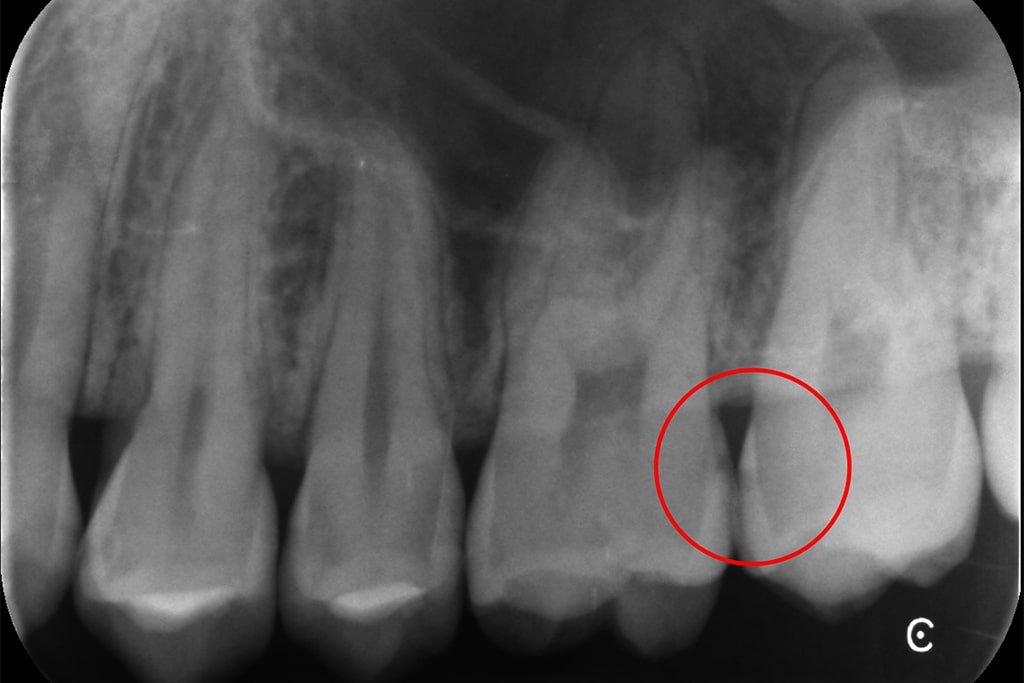

「噛むと痛い」という24歳女性の患者さまの場合

「噛むと痛い」という

24歳女性の患者さまの場合

レントゲン撮影

検査を行い、現在の歯とお口の状態を確認します。

レントゲン撮影により、肉眼では見えにくい部分のむし歯も発見しやすくなります。